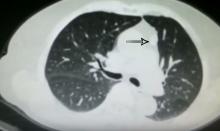

This video shows a thymectomy for a thymic cyst and a wedge resection of a nodule in the right upper lobe. A subxyphoid uniportal VATS approach was used.